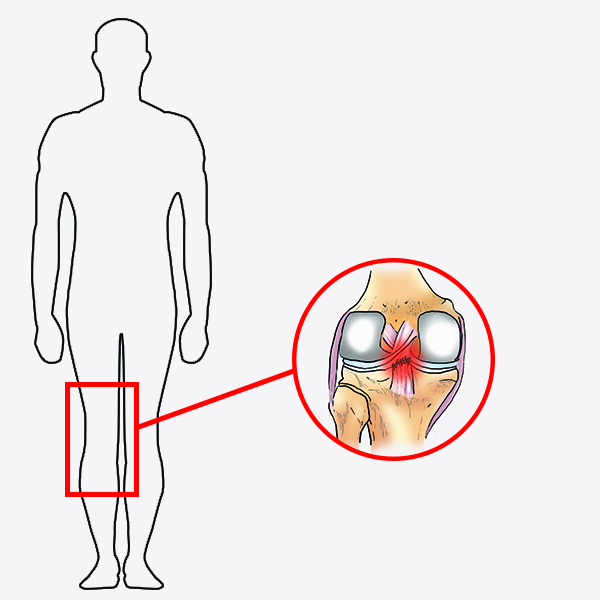

Orteza kolana RAPTOR/2RA stabilizuje staw w płaszczyźnie strzałkowej i czołowej. Orteza RAPTOR/2RA posiada 4-punktowy system podparcia, który doskonale stabilizuje i odciąża staw kolanowy. W przypadku uszkodzonego więzadła krzyżowego tylnego (PCL), kość piszczelowa ma tendencję do nadmiernego przemieszczania się w kierunku tylnym względem kości udowej. Konstrukcja przednio-tylna ortezy pozwala na zabezpieczenie piszczeli i ustawienie jej w osi stawu kolanowego.

W przypadku uszkodzonego więzadła krzyżowego tylnego (PCL), kość piszczelowa ma tendencję do nadmiernego przemieszczania się w kierunku tylnym względem kości udowej. Konstrukcja przednio-tylna ortezy pozwala na zabezpieczenie piszczeli i ustawienie jej w osi stawu kolanowego.

– Niestabilność PCL – Uszkodzenie/zerwanie PCL – Uszkodzenie/zerwanie ACL – Niestabilność MCL/LCL/ACLTo jest wyrób medyczny.